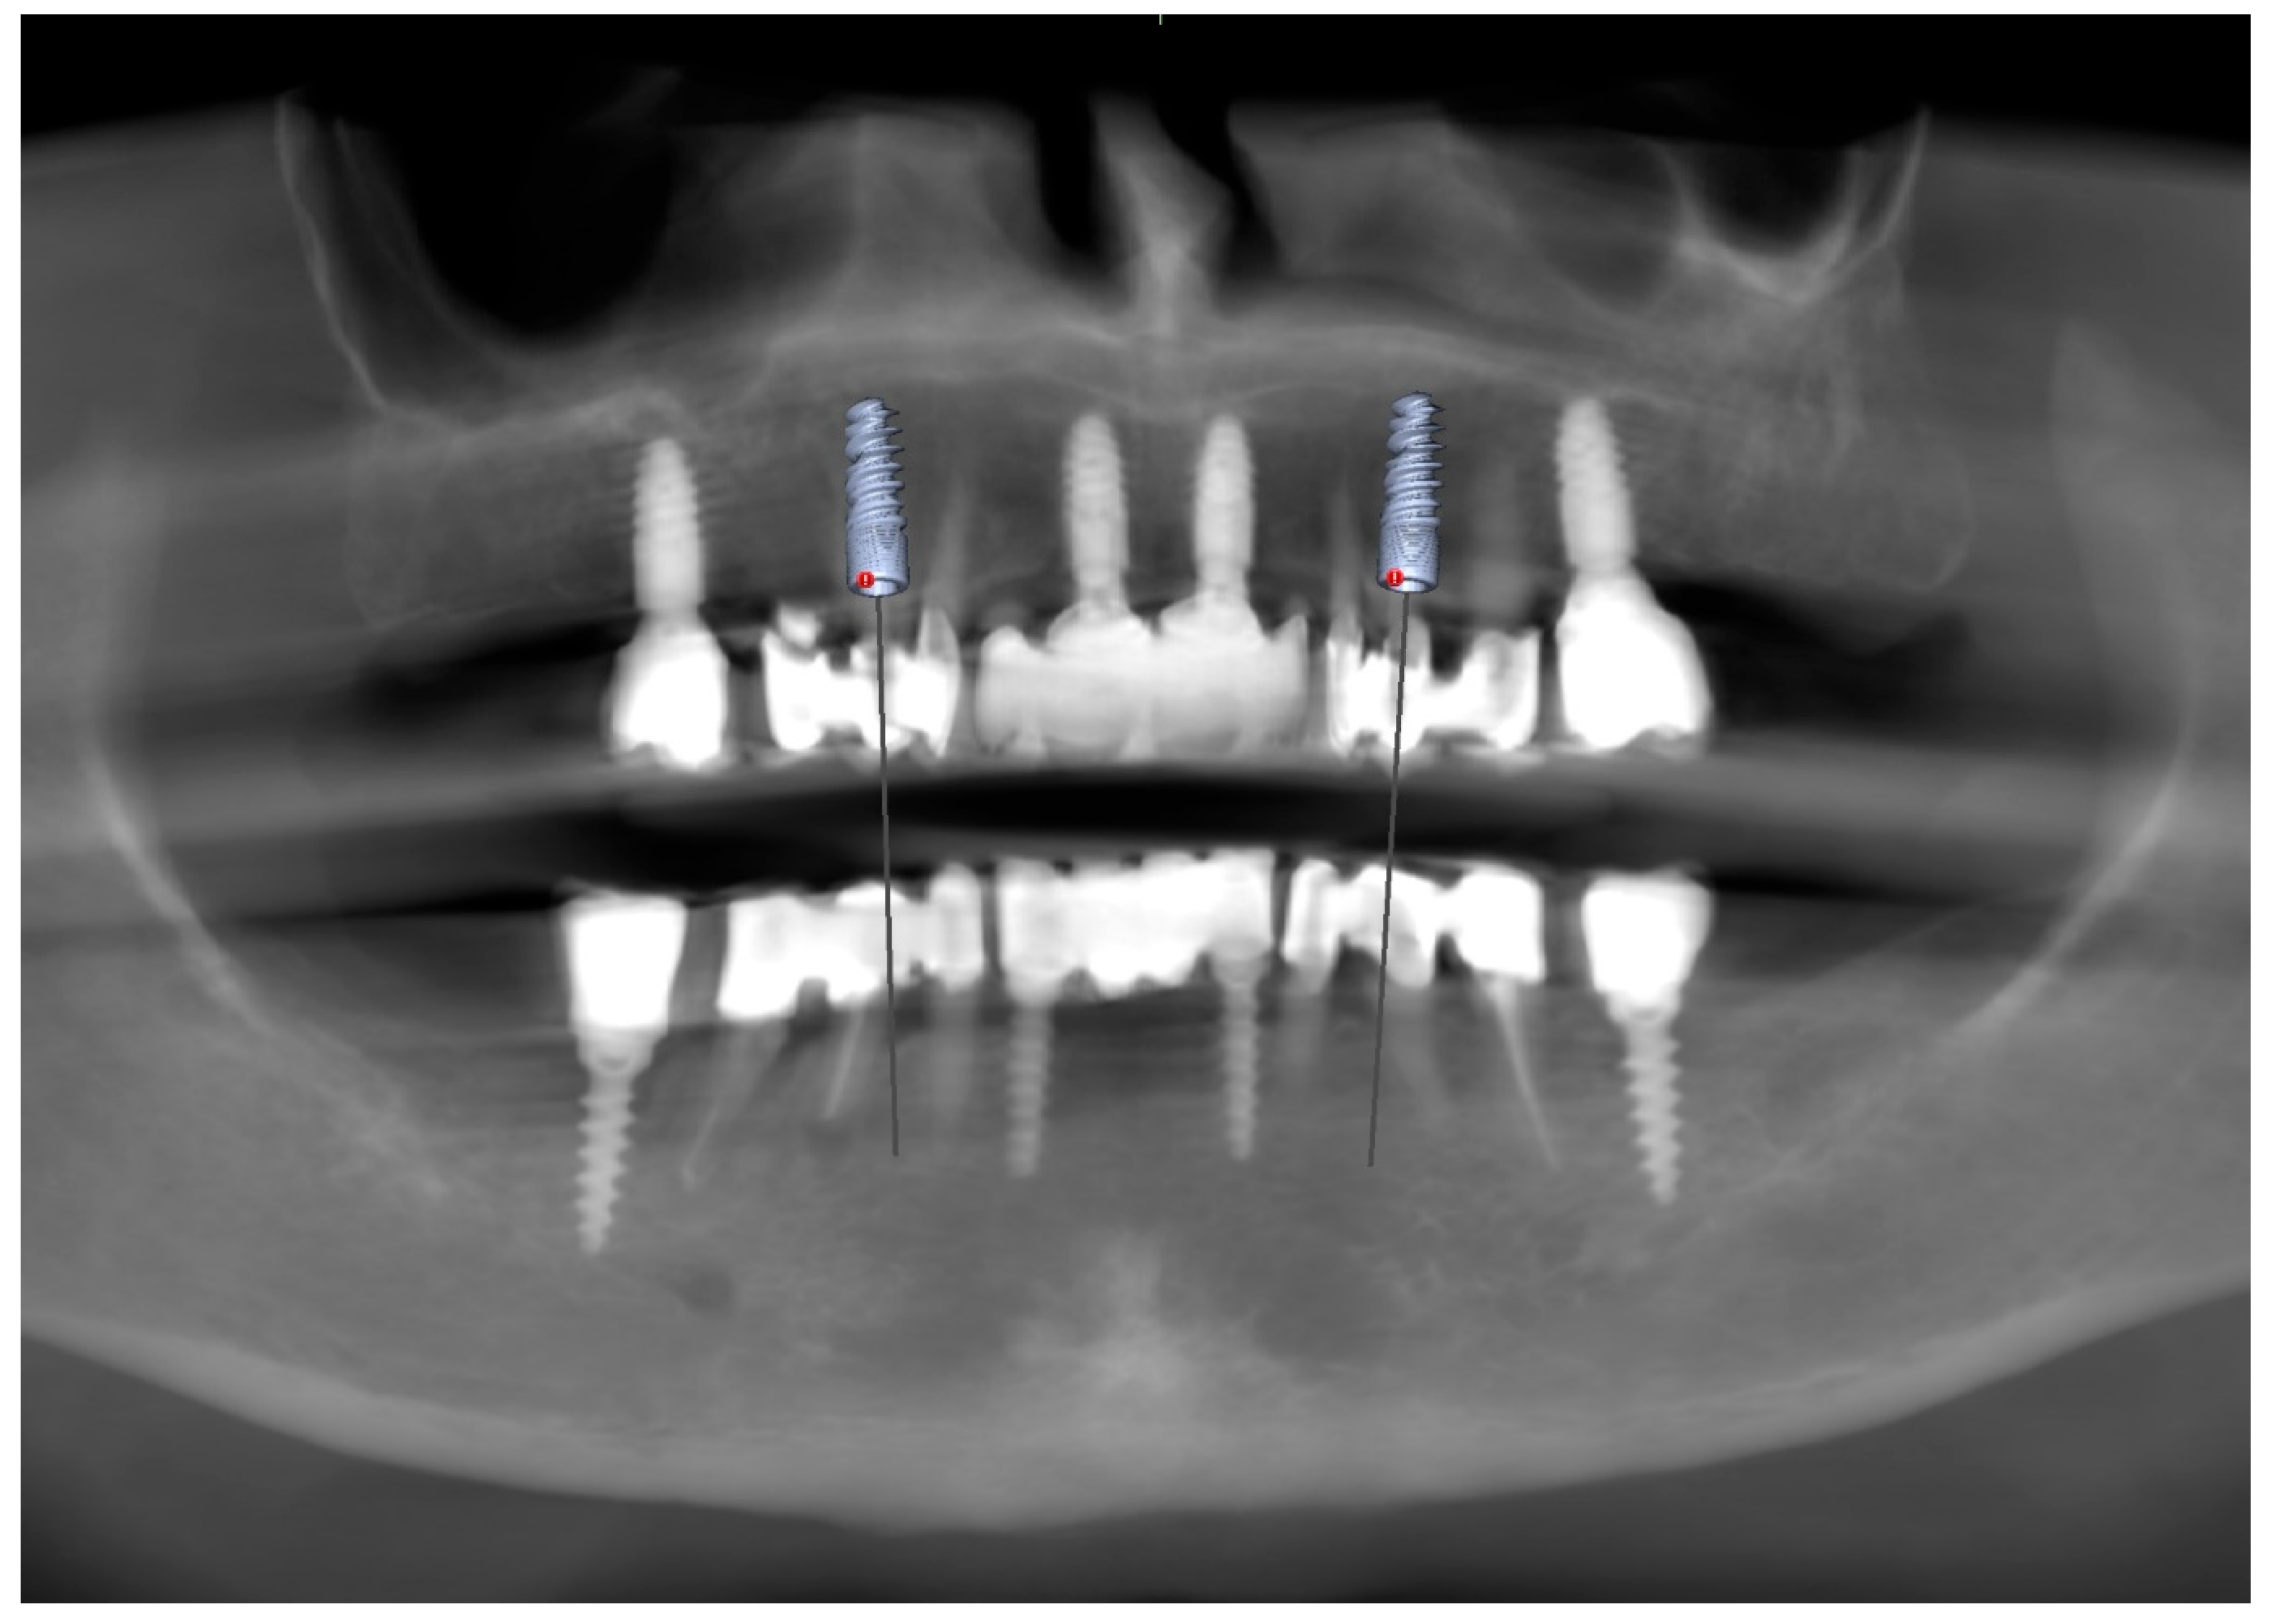

To supplement the clinical findings, a cone beam computed tomography (CBCT) scan was obtained (Figure 1) and evaluated. The implants existing in the maxilla demonstrated proper surrounding bone architecture. The compromised status of the remaining teeth was confirmed. In addition, the available bone conditions in the regions of teeth 14 and 24 were assessed to be adequate for future implant placement, particularly in the context of immediate implant insertion. This is in accordance with the literature emphasising that sufficient bone volume, labial plate integrity, and socket morphology, are critical prerequisites for successful immediate implant placement [7,8,9].

Figure 1. Preoperative panoramic reconstruction from CBCT, showing the initial condition of the existing tooth- and implant-supported restorations in the maxilla and mandible, as well as the visualisation of two planned implants in positions 14 and 24.